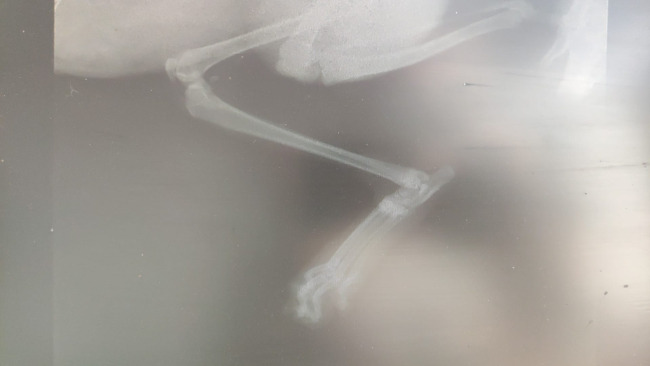

Rita, bo tak nazwał ją obecny dom tymczasowy, trafiła do schroniska ze starym złamaniem, które uniemożliwiało jej funkcjonowanie. Niestety pojawiła się już duża martwica - dlatego pilnie musiała być operowana! Była to skomplikowana operacja zespolenia łapki podczas której została usunięta martwa tkanka oraz została włożona specjalna blaszka, która pozwoli jej na normalne poruszanie się. Na szczęście w łapce jest czucie więc mamy nadzieję, że łapkę uda się uratować.

Koszt operacji to 1500zł, do tego konieczna jest rehabilitacja aby łapka wróciła do sprawności (700zł). Za pół roku konieczna będzie kolejna operacja wyciągnięcia płyty (ok.1500zł) + leki.